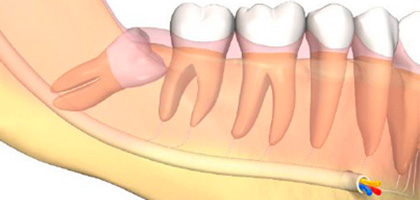

2. 누워있는 사랑니의 인접 어금니(제2대구치)의 충치를 유발하게 됩니다.

3. 염증으로 인해 사랑니 주위의 골이 흡수되어 사랑니 옆의 어금니의 치조골도 함께 흡수 됩니다.